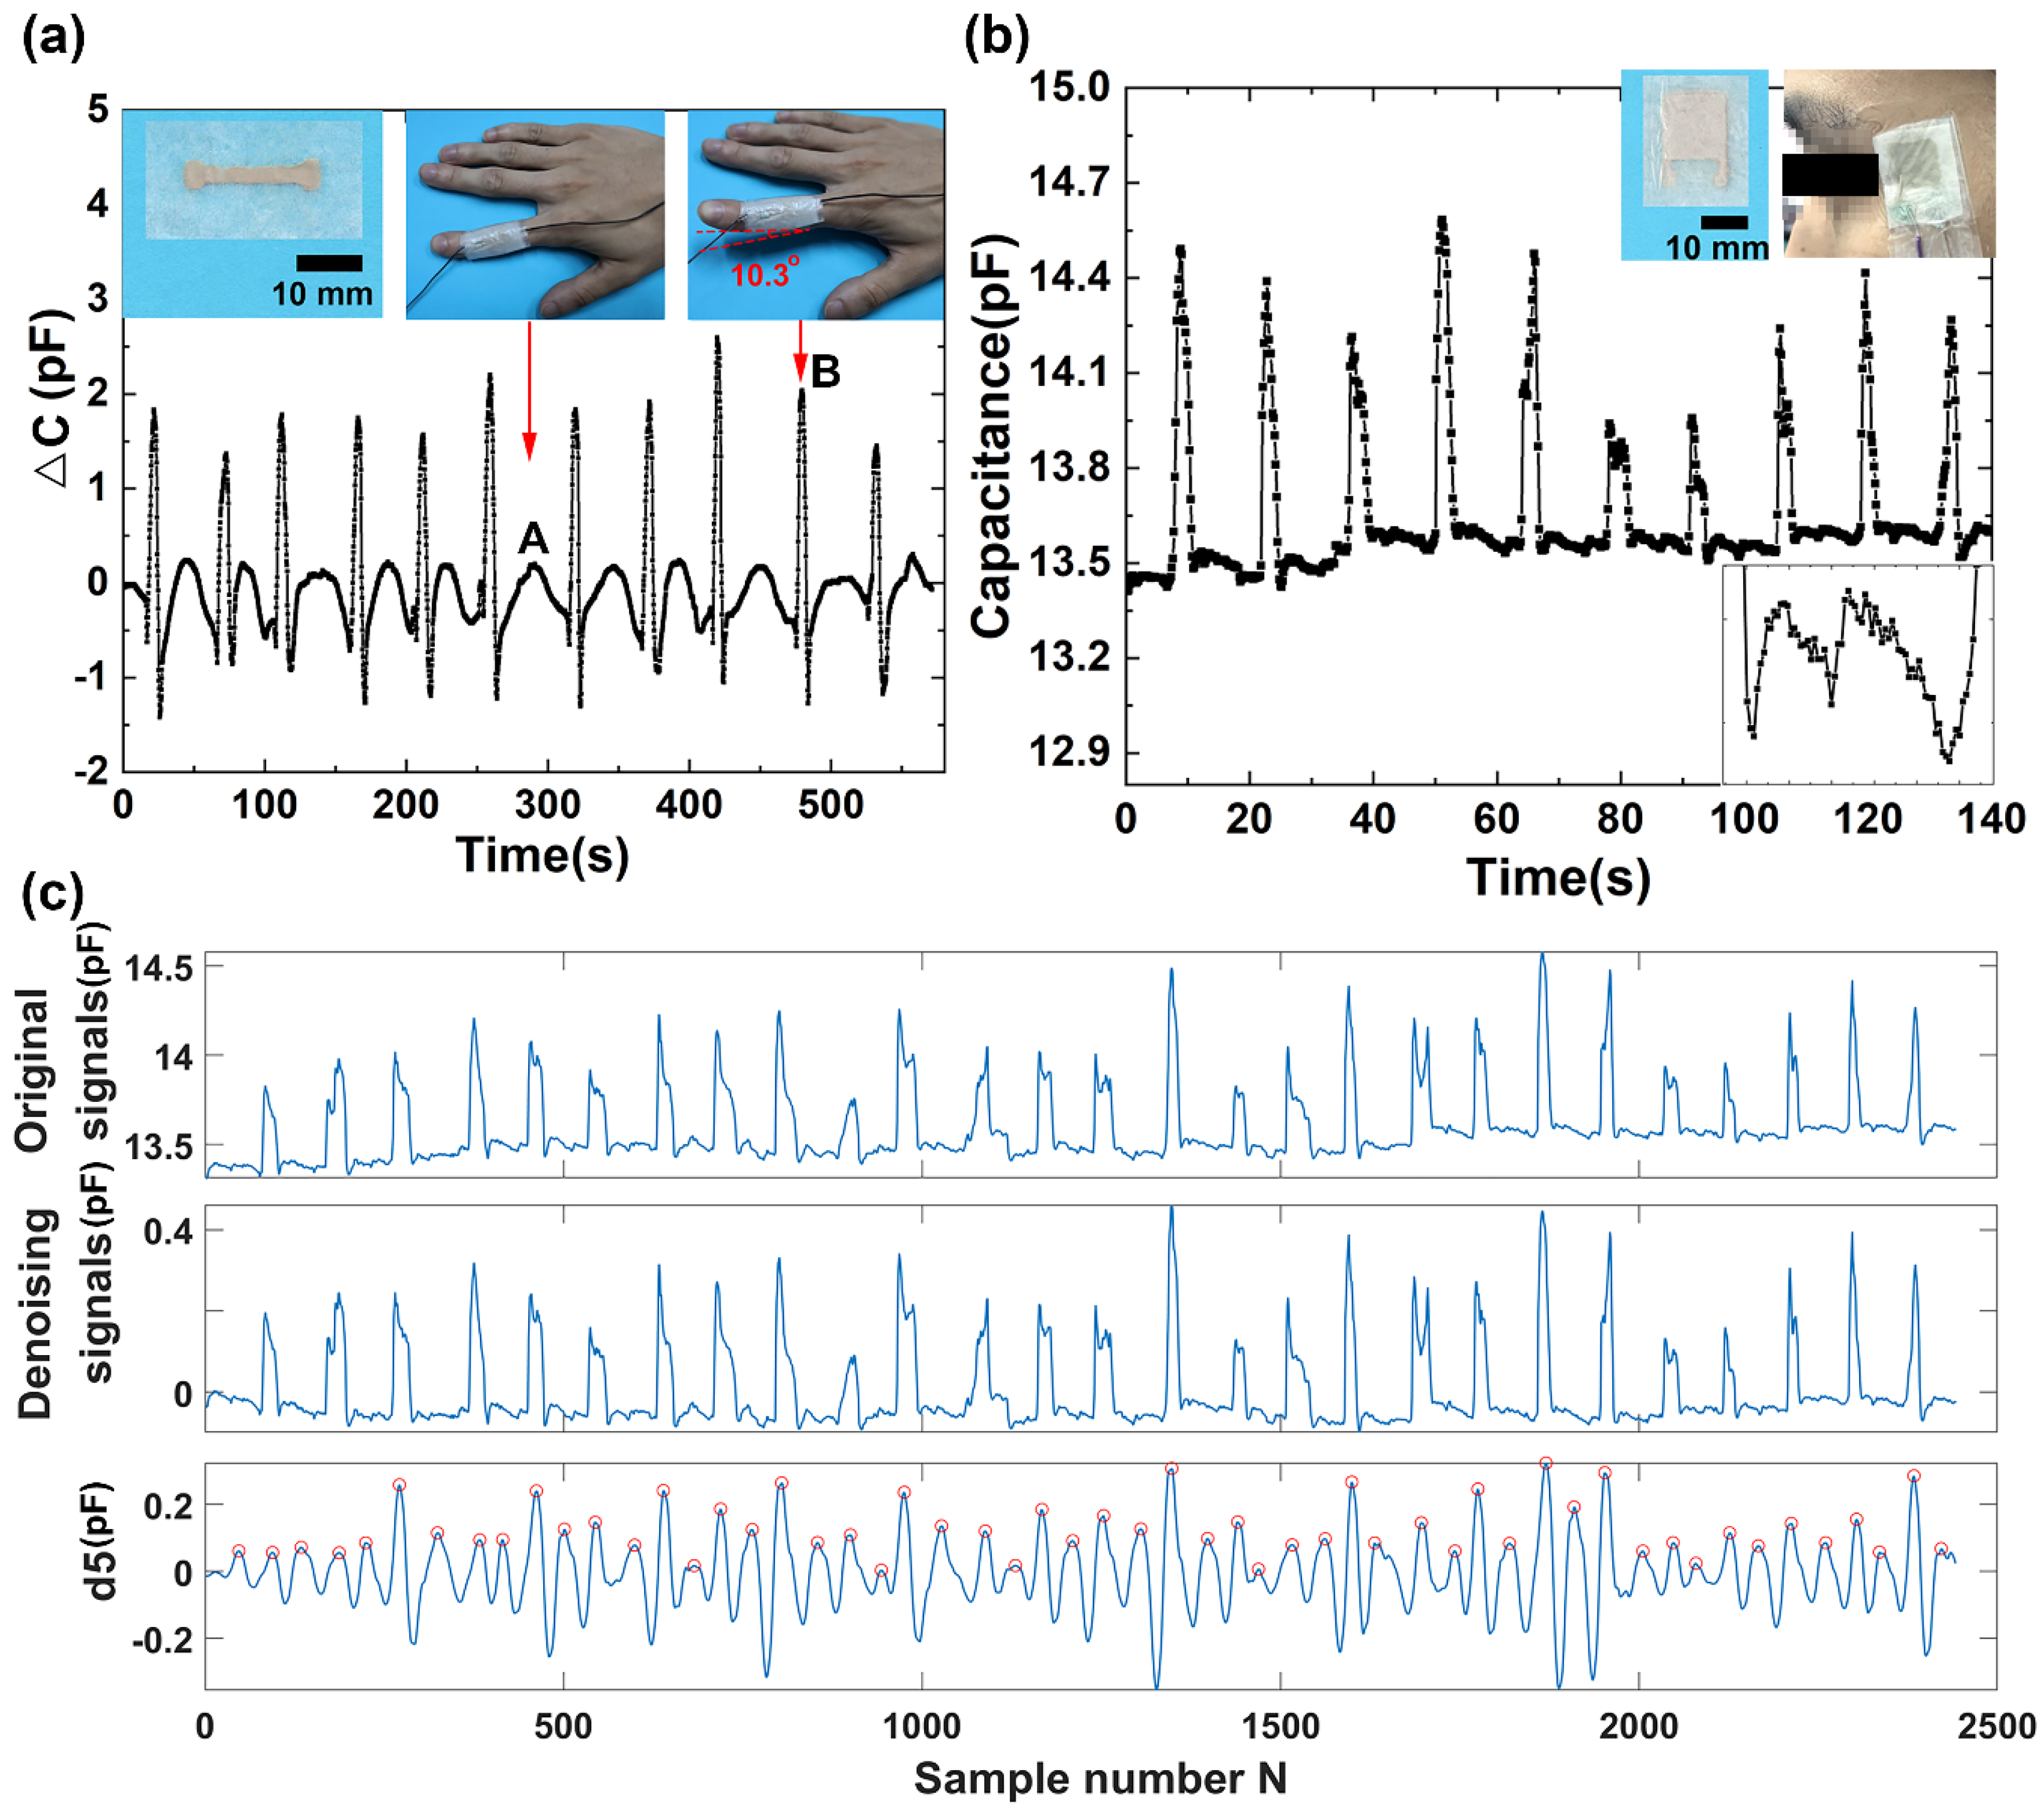

3.3. Monitoring Finger Motion and Eye Blinking

3.4. Detection of Wrist Pulse